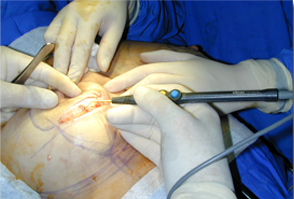

經(jīng)典案例

手術(shù)圖片